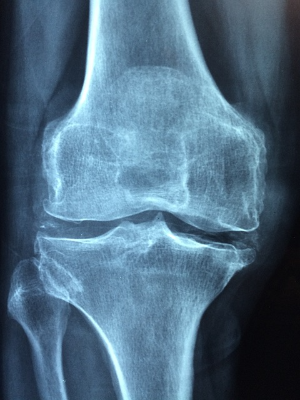

3. 콘드로이친 1200mg 효능 골관절염 진행 완화

게다가, 콘드로이친은 관절염의 진행을 늦추는 것으로 발표되었습니다. 관절염의 특징으로, 연골의 퇴화는 시간이 지남에 따라 관절 손상과 악화로 이어지게 되는데 연구에 따르면 콘드로이친은 연골을 보호하고 보존하는 데 도움을 줄 수 있으며, 잠재적으로 퇴행 과정을 늦추고 관절 건강을 유지할 수 있습니다.

5. 콘드로이친 1200mg 효능 연골 파괴를 줄여줌

콘드로이친 효능 콘드로이친 1200mg은 연골을 보호하는 효과가 있다고 발표됩니다. 이는 연골 파괴를 막아 관절을 튼튼하게 하고 관절이 퇴화되는 것을 늦출 수 있기 때문에, 신뢰할 수 있는 관절 영양제로 오랫동안 관절 건강을 지키시기 바랍니다.